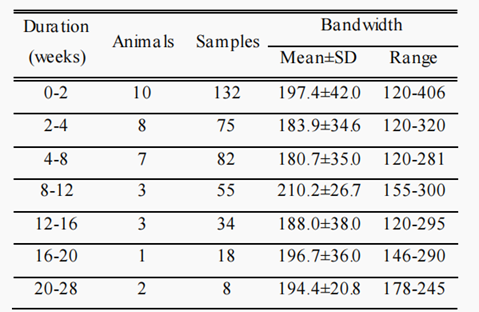

Opie等人进行了一系列实验,探讨了电极植入时间、位置和取向对支架电极带宽的影响。根据电极在导管内部署时所面对的方向,每隔45°放置一次电极。研究植入时间对带宽的影响,动物在植入两周后测量平均带宽为197.4±42Hz(对应于电极整合到血管壁的时间),20-28周时为194.4±20.8 Hz,信号质量没有明显下降。表1显示了描述剩余带宽随时间变化的数据。图5为长期电极植入前后信号采集的最大带宽的变化。

表 1 最大平均带宽、标准偏差和记录的信号范围,从动物植入支架高达190天

图5 植入运动皮层的电极阵列的最大带宽小于7天(n=4),且超过100天(n=6)